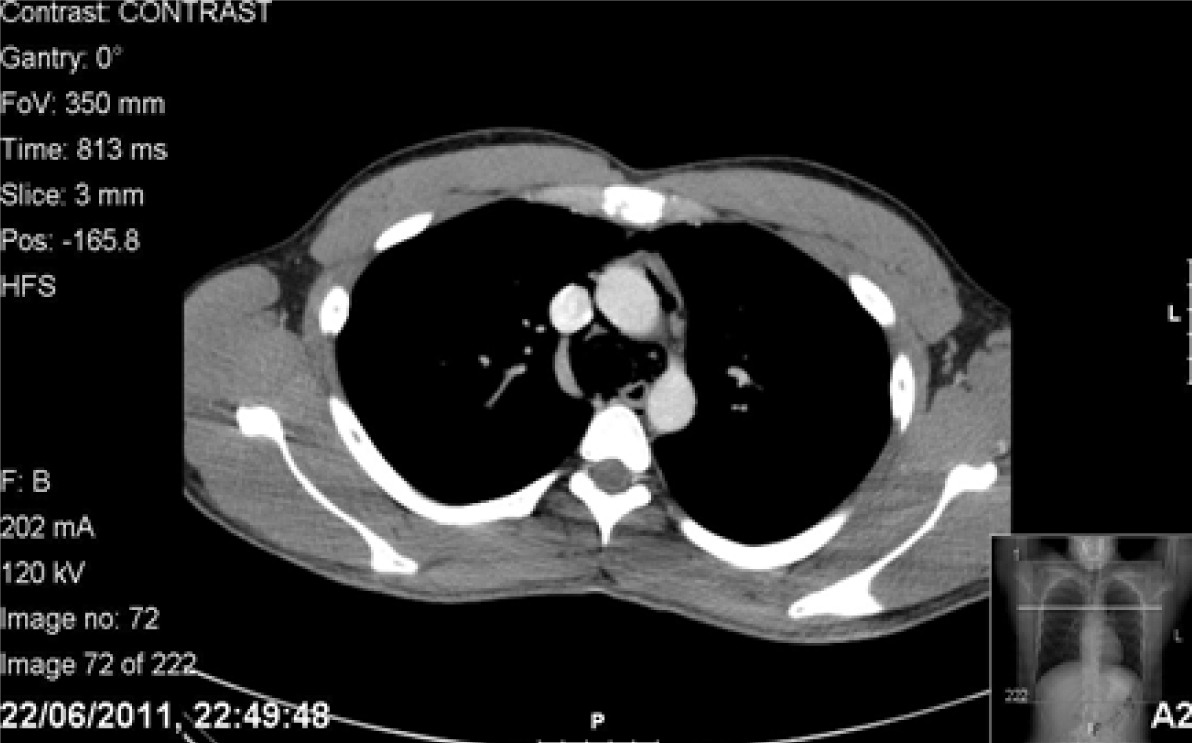

The patient’s symptoms returned spontaneously two days post discharge on the eve of his surgical finals. Subcutaneous emphysema was found on examination. Observations, blood tests and arterial blood gas (ABG) showed no abnormality. Computed tomography scan of chest with IV contrast and Gastrografin swallow showed pneumomediastinum but no leak of Gastrografin. (Figure 2) (Figure 3) Furthermore, there was the dilemma of whether he would be able to sit his exam which was at the same tertiary centre. He was given a stat bag of intravenous fluids, the aforementioned intravenous antibiotics, kept nil by mouth and allowed home to rest. He was admitted directly after his surgical finals and treated conservatively. Nutritional support was given via a nasogastric tube which was inserted under radiological guidance. The patient’s symptoms improved and a Gastrografin swallow study on day-10 was normal. Soft diet was commenced which he tolerated. The patient’s second hospital stay was 12 days. He continued with a fork mashable soft diet until his three month follow-up, which was satisfactory, returning to a normal diet thereafter. Thankfully, the patient passed his finals and continues to work as a doctor. (Figure 4) (Figure 5)

Figure 4: Computed tomography scan of chest with Gastrografin contrast; comparison of image on admission and image after resolution showing no pneumomediastinum.